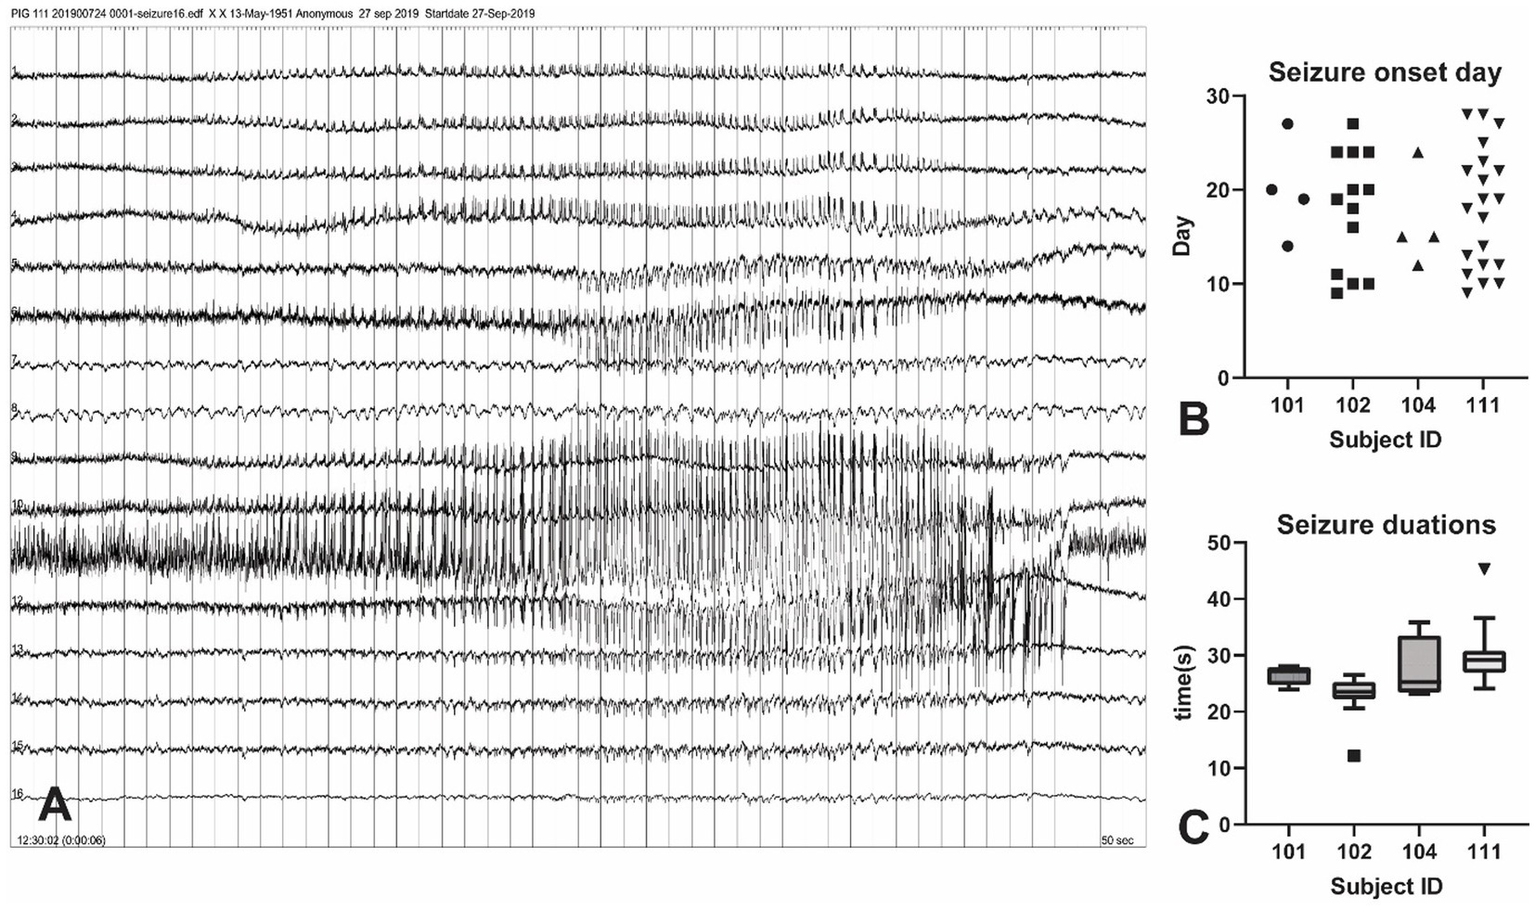

A total of 46 tonic-chronic electrophysiological seizures were identified in the 4-week post-KA period from four pigs (Figure 3). The earliest seizure onset was at day 9 (in subject 102) and the latest was recorded at day 28 (the last day of measurement). The average seizure onset day was (18 ± 5.96), and the number of onsets was 4, 13, 4, and 20 in each animal. The seizure duration ranged from 12 to 45 s (mean = 27.21 ± 5.20).

Figure 3

Seizure events in the KA-pig model of epilepsy. (A) Screenshot of a tonic–chonic electrophysiological seizures onset in an animal after KA injection. The onset is located in channel 11, later confirmed to be the right hippocampus. A total of 46 electrophysiological seizures were captured in the 4-week post-KA period from 4 animals (25% of the total). (B) The analysis of the seizure onset day. The earliest chronic seizure onset was observed in animal 111, on day 9 (shown in Figure A), and the last one was on day 27. The first seizure onset day is from 9–14 in these animals. (C) Seizure durations from all recorded 46 seizures in 4 pigs. The seizure duration ranged from 22 s to 35 s.